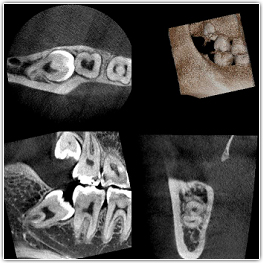

難しい症例も高い技術と経験で抜歯可能です。

はぎわら歯科は抜歯の技術に自信があります。最新の設備・高い技術力・長年の経験から、難しいとされる事例も的確な処置で安全に抜歯を行います。難しいケースはCTにより精査します。大学病院へ紹介される歯科医院も多いと思いますが、大学病院へ行く時間のとれない方は当院にて対応いたします。他の歯科医院の先生からも数多く依頼を受けています。